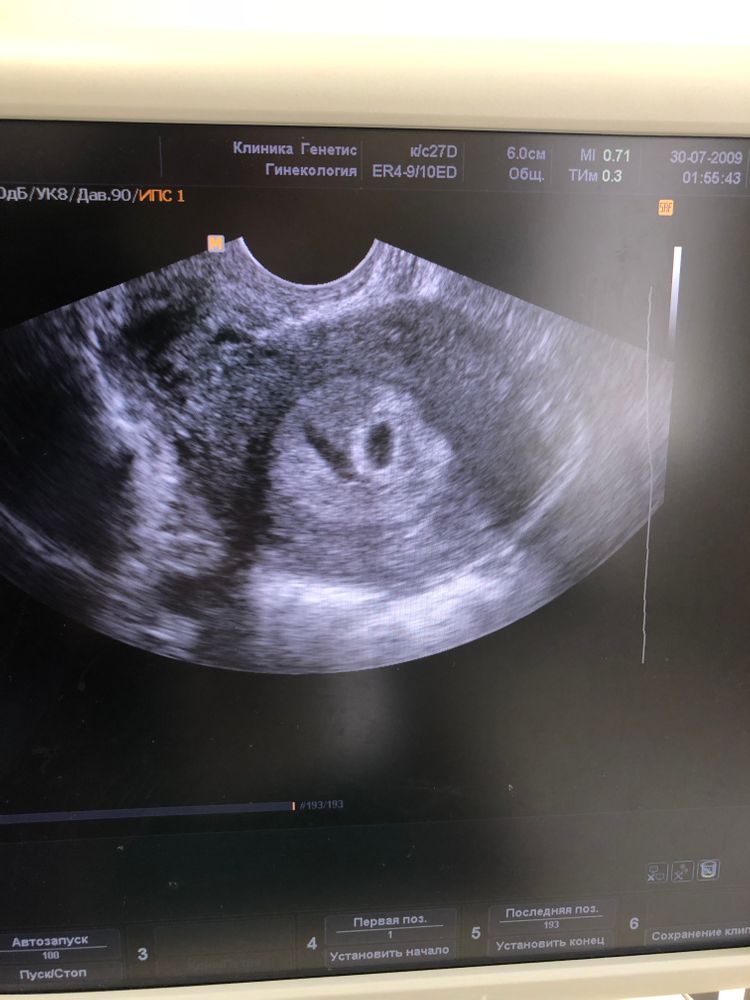

Узи.5-6 недель Яичники